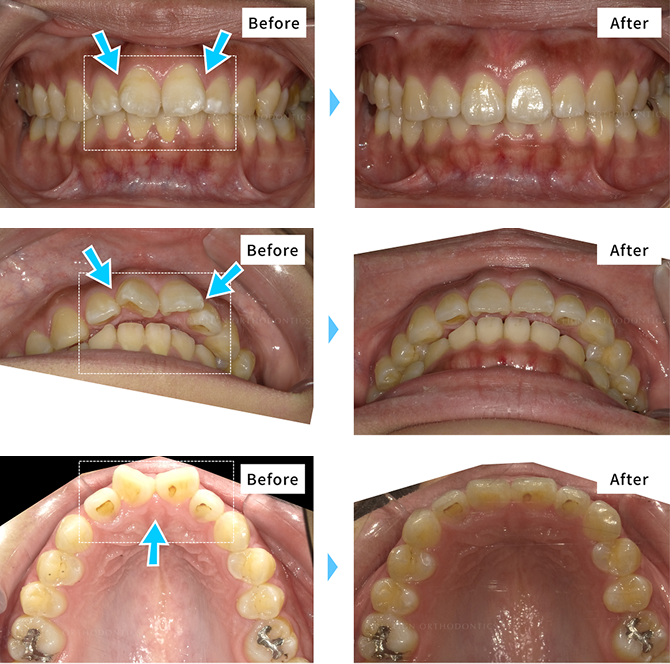

矯正治療の症例

キレイラインを7回実施

- [ 治療期間 ] 約7ヶ月半

- [ 治療費用 ] 290,000円

(税込319,000円)

- [再診料] (5回 15,000円 (税込16,500円)

- [追加治療] 上顎左右2番矮小歯の補綴

※効果には個人差があります。

※補綴・治療の費用は各提携クリニックによって異なります。